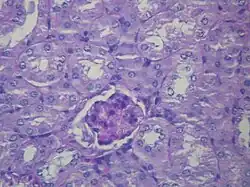

Microscopic image of diabetic glomerulosclerosis, the main cause of nephrotic syndrome in adults.

Diabetic glomerulonephritis in a person with nephrotic syndrome.

Secondary causes of nephrotic syndrome have the same histologic patterns as the primary causes, though they may exhibit some differences suggesting a secondary cause, such as inclusion bodies.[24] They are usually described by the underlying cause, such as: